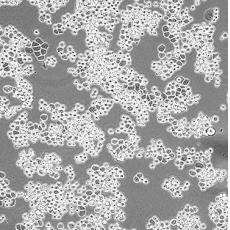

MDA-MB-453

產品名稱 MDA-MB-453

中文名稱 人乳腺癌細胞

組織來源 乳腺腺癌;胸腔積液轉移;女性

生長特性 adherent

形態特征 epithelial

細胞描述 該細胞系由CailleauR在1976年從一名48歲的患有轉移性乳腺癌的白人女性的心包滲出液中分離建立的。該細胞表達FGF的受體。